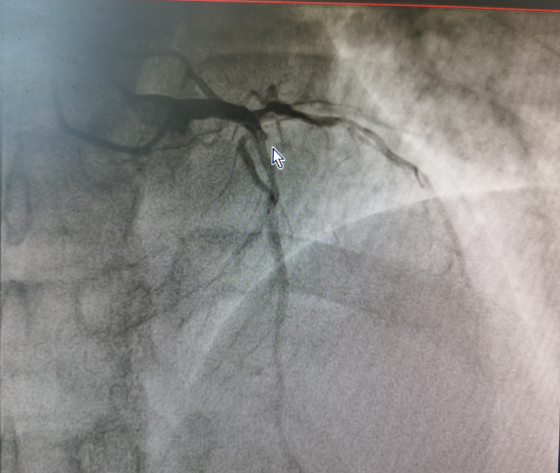

▲患者心血管造影图▲

明确诊断为急性心肌梗死后,立即为患者开通胸痛绿色通道进行抢救,给予患者口服“阿司匹林300mg、阿托伐他汀40mg、替格瑞洛180mg”并静脉注射“普通肝素”抗凝。与家属沟通告知病情,建议立即行冠脉介入手术治疗。患者及家属同意手术后,通过胸痛绿色通道,从我院二马路院区直达文峰院区介入室。冠脉造影术提示前降支血管壁不光整,近段管腔狭窄约60%,高位对角支闭塞;前向血流TIMI0级,于对角支闭塞处植入2.25mm×24mm药物支架1枚,术后收住心血管内科继续住院治疗。从患者到达门诊到行球囊扩张使冠状动脉再灌注治疗时间仅仅为36分钟,实现了生命通道的无缝衔接,使患者得到了高效的救治。目前,患者已顺利康复出院,恢复发病前的工作生活能力。